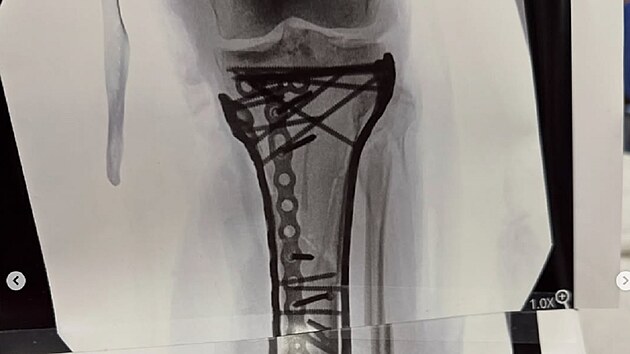

Dvojnásobná mistryně světa při pádu v Cortině d’Ampezzo utrpěla komplexní zlomeninu holenní kosti. V Trevisu absolvovala postupně čtyři operace, v pondělí odletěla do Ameriky, kde se nyní podrobila dalšímu zákroku.